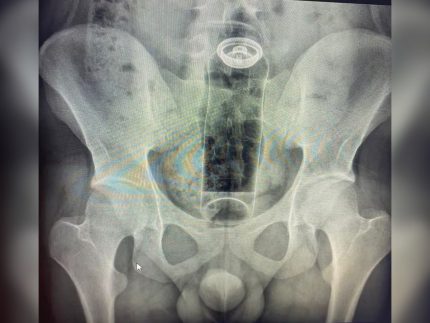

Uma “brincadeira” íntima terminou em caso de emergência médica para um jovem de 19 anos, que precisou ser internado para retirar um frasco de desodorante que ficou preso em seu reto. O rapaz buscou ajuda hospitalar após perceber que o objeto havia migrado para a parte interna do intestino, tornando impossível a remoção manual em casa.

A internação foi necessária para realizar o procedimento de retirada com segurança, já que tentativas caseiras ou o uso de laxantes poderiam agravar o quadro. A permanência de corpos estranhos no local oferece riscos gravíssimos à saúde, podendo causar perfurações no intestino, infecções generalizadas e, em casos extremos, levar ao óbito.